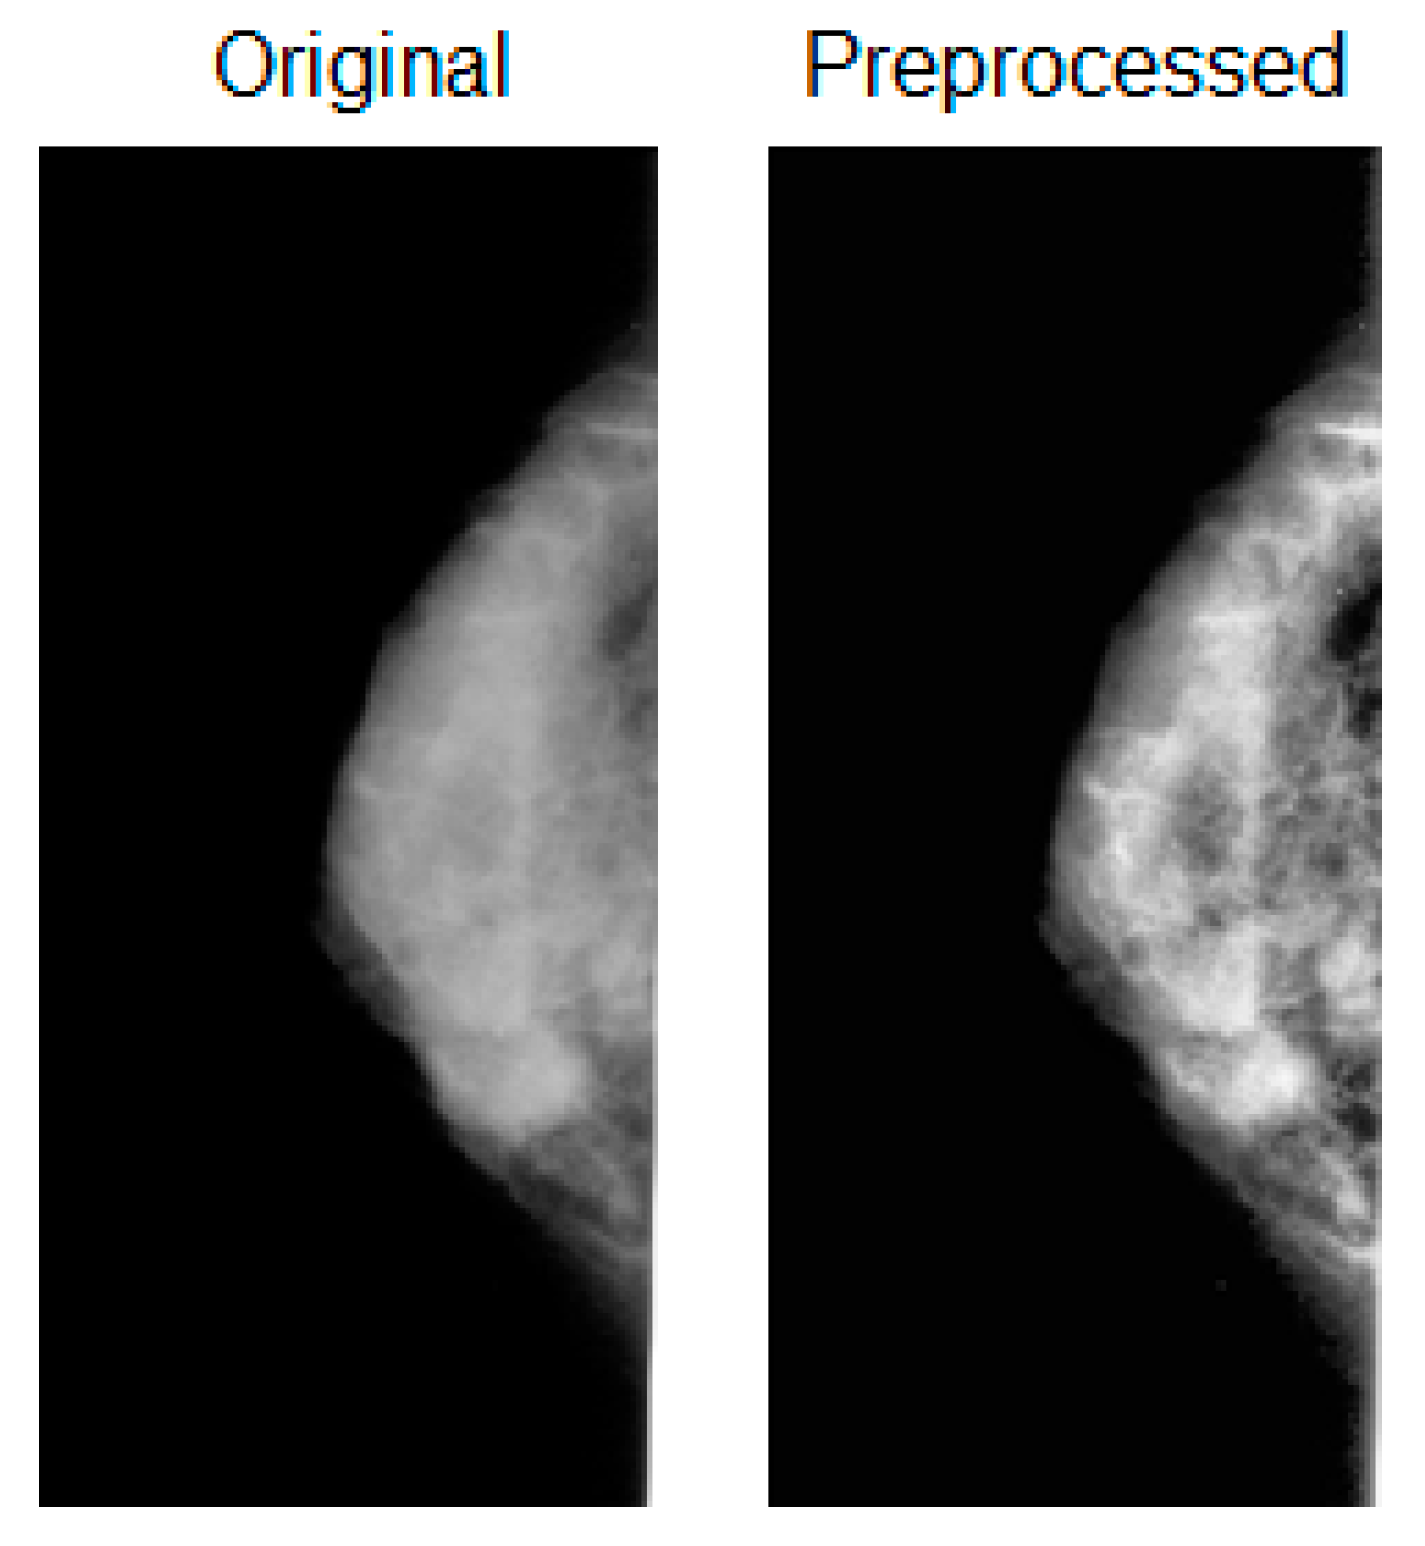

2.3. Preprocessing